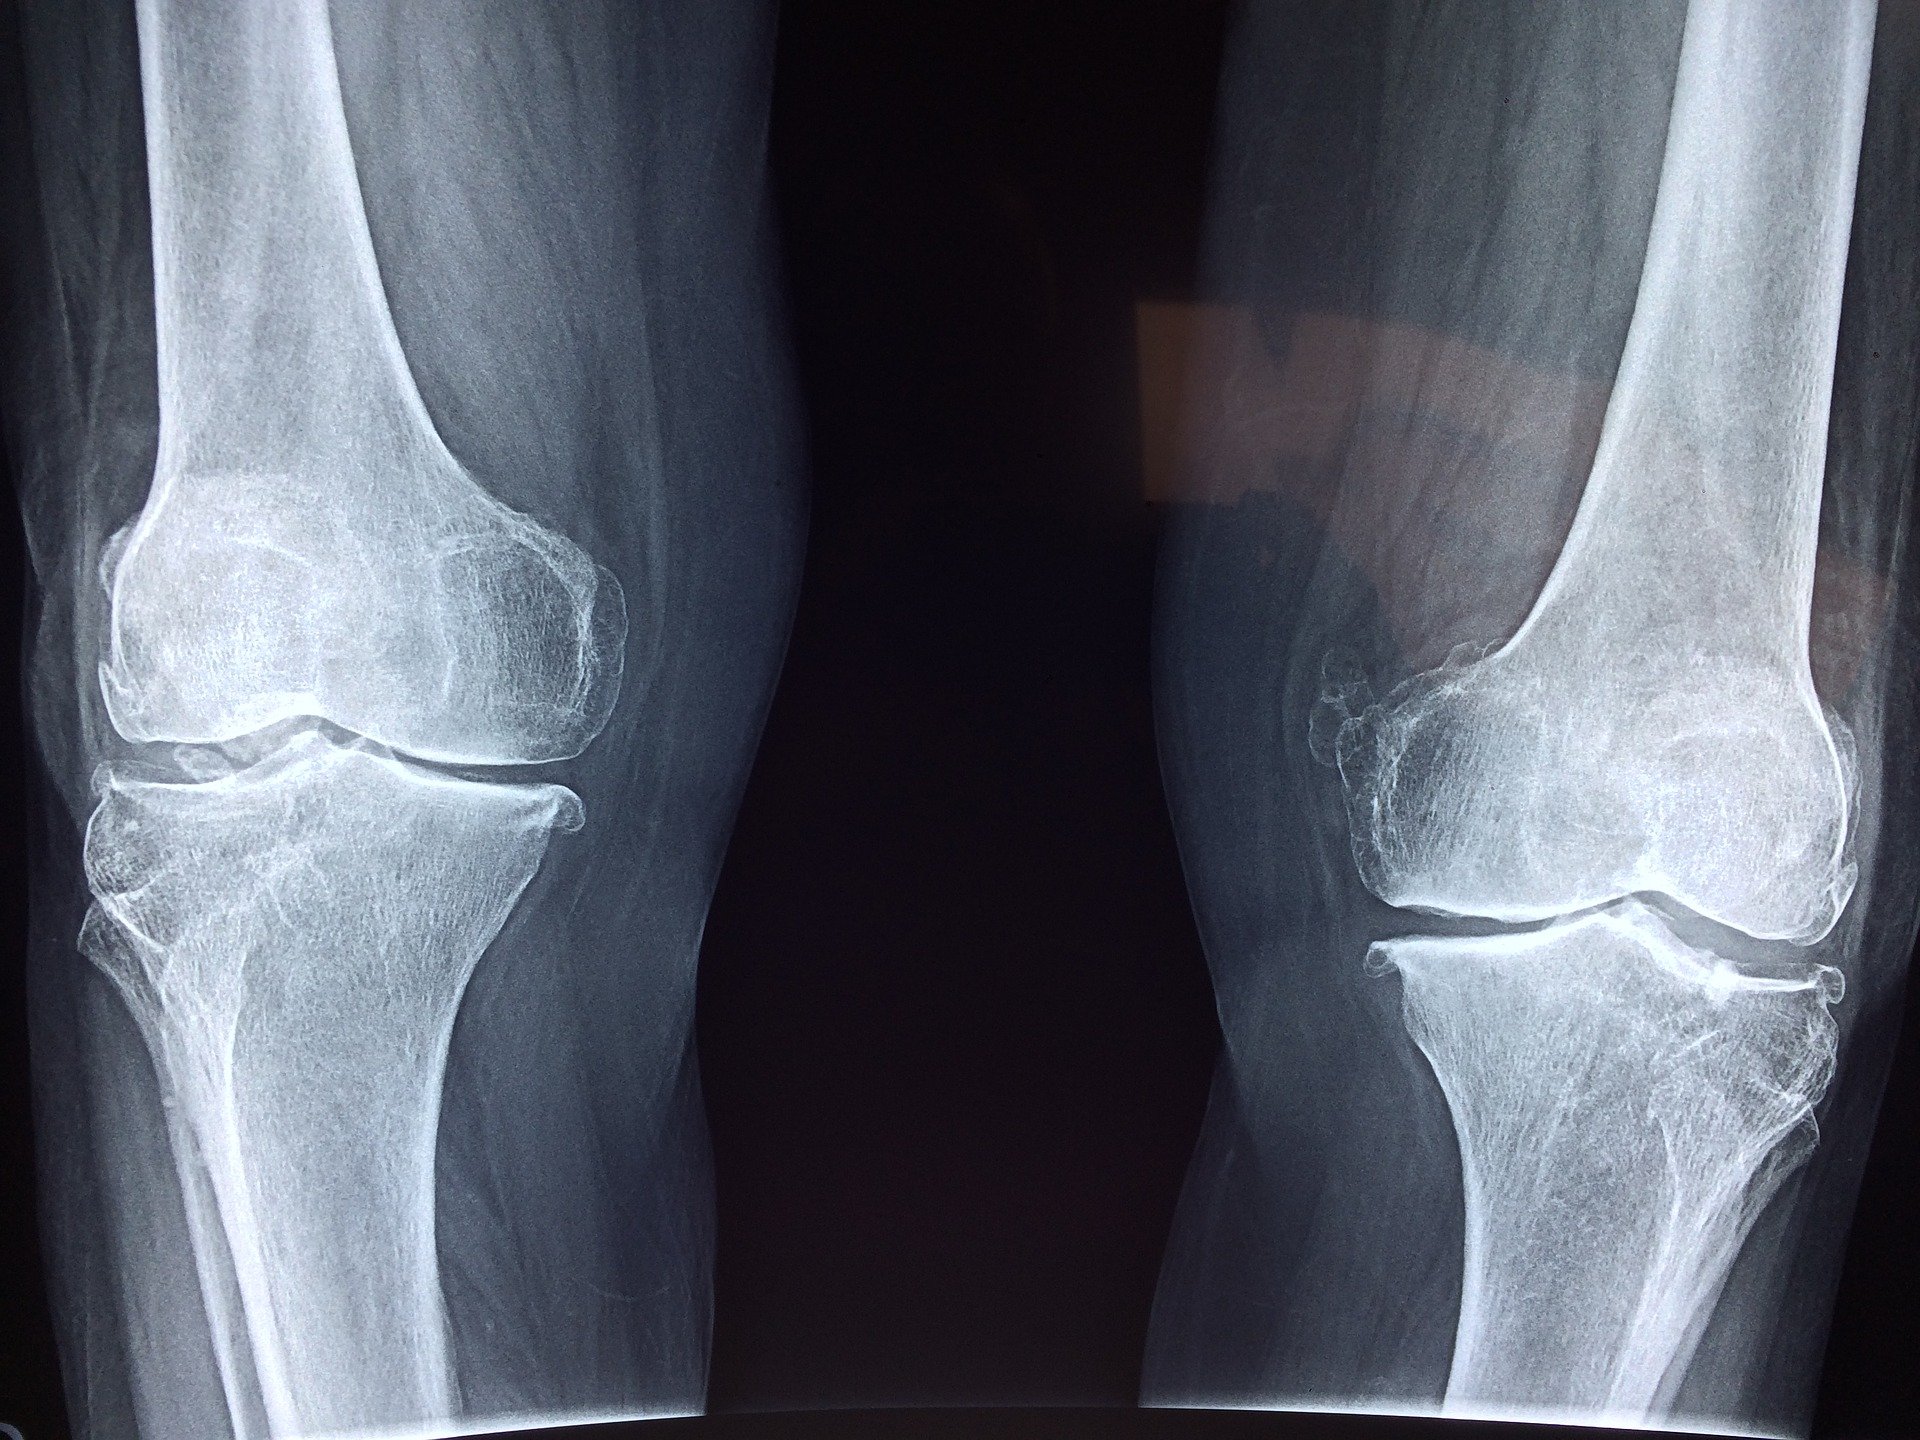

O to starożytna technika stosowana przez sportowców w celu zmniejszenia obrzęku i bólu kolan. Spuchnięte kolana mogą być oznaką innych problemów zdrowotnych. Jeśli problem nie ustępuje lub nasila się, należy skonsultować się z lekarzem. Te domowe sposoby można zastosować, jeśli początkowo ból nie jest silny.